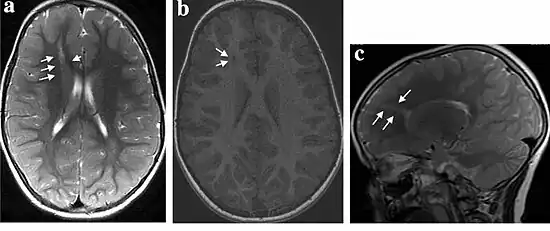

| MRI of a child experiencing seizures. There are small foci of grey matter heterotopia in the corpus callosum, deep to the dysplastic cortex. (double arrows) | |

Gray matter heterotopia is a neurological disorder caused by gray matter being located in an atypical location in the brain.[1] Grey matter heterotopia is characterized as a type of focal cortical dysplasia. The neurons in heterotopia are otherwise healthy; nuclear studies have shown glucose metabolism equal to that of normally positioned gray matter.[2] The condition causes a variety of symptoms, but usually includes some degree of epilepsy or recurring seizures, and often affects the brain's ability to function.